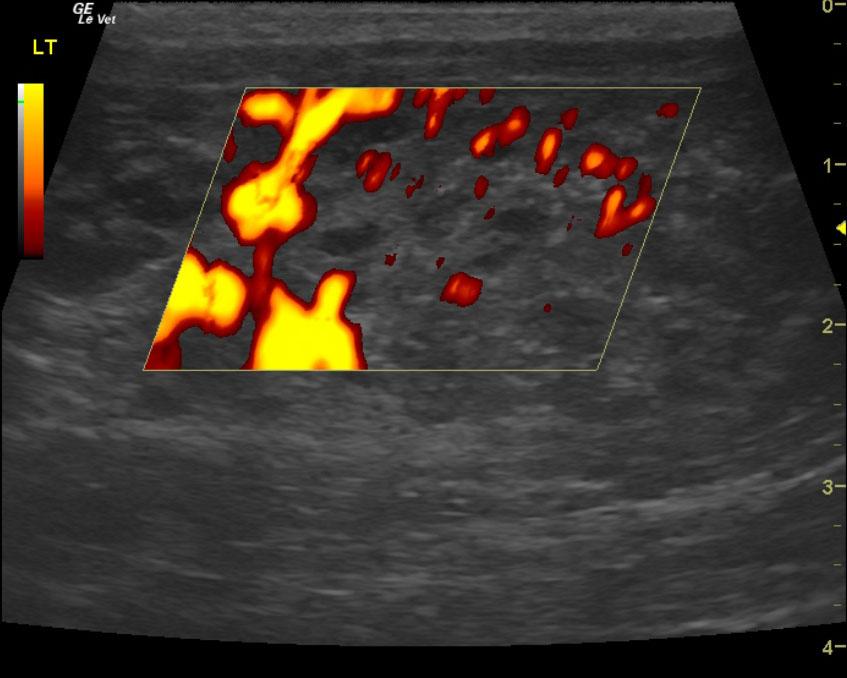

A 9-year-old male neutered Plotthound dog was presented for evaluation of polyuria, polydypsia, and occasional loose stool. Abnormalities on CBC and serum biochemistry included mild anemia, mild leukopenia, mildly increased ionized calcium, and mild azotemia. T4 was within reference range at 4.4.